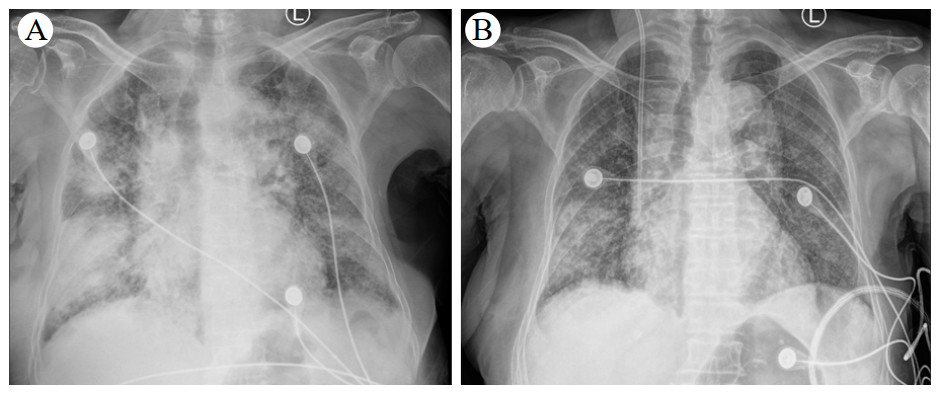

患者仍然诉胸闷,呼吸窘迫、咯血,伴有血色素进行下降,2次粪便隐血试验阳性。患者既往有股骨头坏死和肿瘤病史,拒绝激素冲击和免疫制剂治疗。为尽快改善症状,行血浆置换术(3 000 mL,qd),继续维持甲泼尼龙原治疗,加强护胃。经过连续5次血浆置换后,呼吸困难、咳嗽明显改善,无咯血。2022-03-29患者高流量吸氧改为普通吸氧,3.0 L/min,各项检查值:SaO2 97%~99%,WBC 8.16×109/L、中性粒细胞计数(NEUT)7.56×109/L、HGB 82.00 g/L。CRP 7.06 mg/L,IL-6 4.10 pg/mL,PCT 0.16 ng/mL,ESR 15.1 mm/h,Scr 111.20 μmol/L,总胆红素(TBIL)26.62 μmol/L、白蛋白(ALB)39.32 g/L、肝功能、电解质正常。核周型抗中性粒细胞胞浆抗体(典型)弱阳性、抗核抗体(ANA)强阳性、ANA滴度1∶100,天然SS-A抗体弱阳性、抗Ro-52抗体弱阳性、抗SS-B抗体弱阳性,抗心磷脂抗体阴性。胸部DR提示:双肺见片絮状高密度影,较前改善(图 2B)。2022-03-31复查胸部CT提示:双肺见多发磨玻璃样及片状高密度影,部分实变,较前吸收好转(图 3)。患者自动出院,出院口服泼尼松(40 mg,1次/d)和羟氯喹(200 mg,2次/d)治疗,并序贯减量,出院后2周(见附图 1A和图 1B)以及第6周胸部CT(见附图 1C和图 1D)随访较前进一步改善。

| 图 3 患者2022-03-31胸部CT检查影像 |